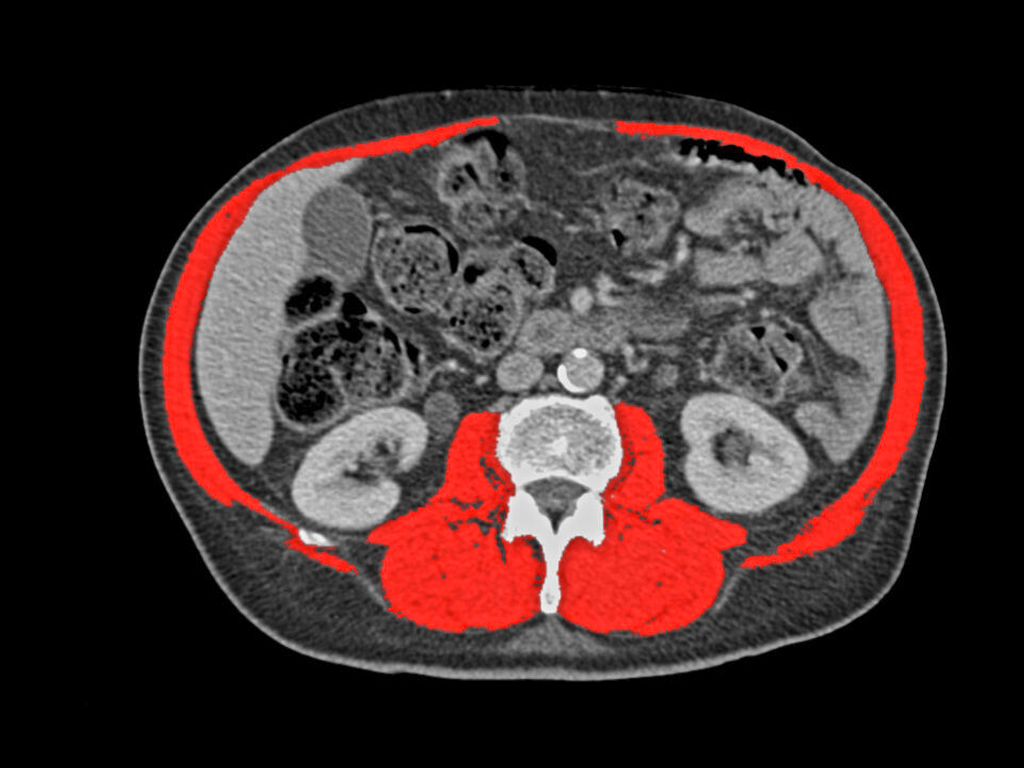

Durch die bei jedem Patient/jeder Patientin durchgeführte CT wird es ermöglicht, den Muskelstatus bzw. eine Sarkopenie zu quantifizieren und zu diagnostizieren (Abb. 2). Eine rezente Analyse aus unserem Zentrum hat gezeigt, dass sarkopene Lungenkarzinompatient:innen eine signifikant geringere postoperative 5-Jahres-Gesamtüberlebensrate aufweisen (64,5 vs. 75,6%).4 Bei Kenntnis dieser Sarkopenie kann eine Prähabilitation gefährdeter Patient:innen eingeleitet werden, um die postoperative Komplikationsrate und damit auch den stationären Aufenthalt zu reduzieren.5 Eine randomisiert-kontrollierte Studie von Liu et al. hat gezeigt, dass bereits zwei Wochen Prähabilitation zu einer signifikanten perioperativen Verbesserung beim 6-Minuten-Gehtest führen.6 Eine Schädelbildgebung ist laut den„Tiroler Arbeitskreis für Onkologie“(TAKO)-Empfehlungen nicht bei allen Lungenkarzinompatient:innen notwendig. Sollte jedoch bei fortgeschrittenen Stadien ein kurativer Ansatz verfolgt werden, so ist eine entsprechende Bildgebung definitiv zu empfehlen. Prinzipiell kann eine CT oder Magnetresonanztomografie (MRT) durchgeführt werden, jedoch sollte laut ESMO bei Verfügbarkeit ein KM-MRT präferiert werden.1 Dies ermöglicht eine sensitivere Diagnostik.

Abb. 2: Sarkopenie-Quantifizierung mithilfe der Staging-CT